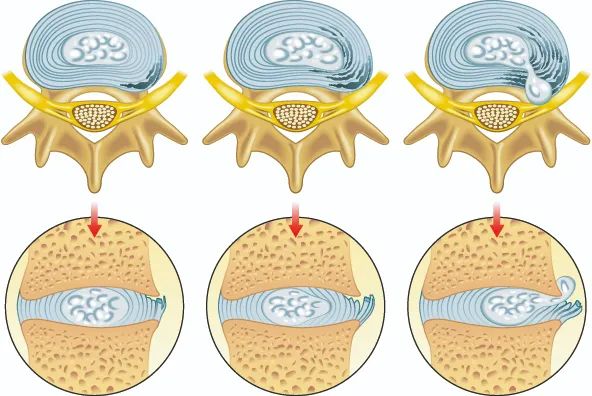

多数患者有腰痛,当神经根受到刺激,疼痛放射至下肢,引起坐骨神经痛,典型的坐骨神经痛是从腰骶部向臀部、大腿后外侧、小腿外侧至足部,呈放射痛。

在腹压增加时疼痛加重。高位腰椎间盘突出表现为股神经的损害。

是突出的椎间盘压迫本体感觉和触觉纤维引起的。少数患者自觉下肢发凉、无汗。

椎间盘向后正中突出或髓核脱出时可压迫马尾神经,患者可出现会阴部麻木、刺痛,大小便功能障碍,阴茎勃起障碍等。